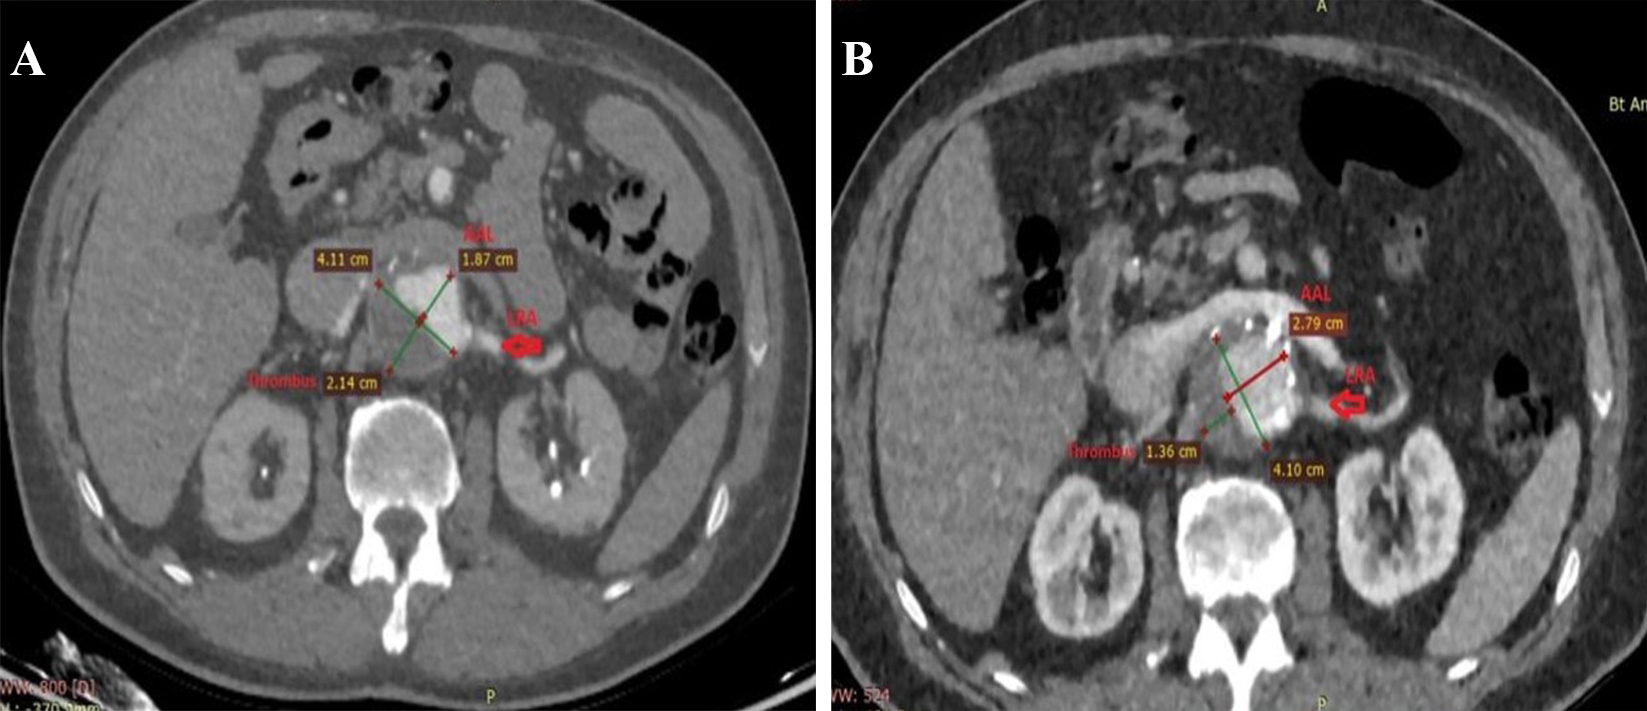

One patient also had a contained rupture in the thoracic segment. There was a heavy thrombus burden in 5 patients circumferentially involving nearly 25-50% of the neck (Fig. 2A,B).

Fig. 2.Remodeling of thrombus and true lumen in the aneurysm after Funnel EVAR. Preoperative thrombus burden at the infrarenal neck (A) and postoperative diminished thrombus burden and enlarged active lumen with no infrarenal neck enlargement at 48 months CTA control (B). EVAR, endovascular aneurysm repair; CTA, computed tomographic angiography; AAL, aortic active lumen; LRA, left renal artery.

Wide necks over 28 mm tend to have more Type Ia endoleaks and require late interventions [2, 3, 4]. Patients with wider proximal aortic necks also have shorter necks and larger aneurysm diameters. This may be the reason for the higher morbidity rates. We think that the most complex issue for this technique is placing the endograft at the diseased aortic segment. In the ageing aorta, there is ongoing aneurysmal disease as the aortic wall structure is negatively altered in a progressive manner. In our experience, we did not face any neck enlargement and no aneurysm-related complications. Tassiopoulos et al. [19] reported that small necks appear to be at higher risk for subsequent dilatation whilst matching the size of the endograft. Amongst the different Funnel-EVAR techniques, although it depends on the availability of the endograft sizes, using a longer thoracic endograft may create the possibility of sideway movements and result in Type III endoleaks [10, 12, 16]. Using aorto-uni-iliac endografts may alter the patency of extra-anatomic bypass grafts [8]. After standard EVAR, AND may develop with an incidence of 20–28% at two years and up to 43% after open surgical repair [17, 18, 19, 20]. Ongoing aneurysmal disease or the radial force of the oversized endograft may be the reason for this complication. No neck enlargement was demonstrated in our midterm follow-up period (Fig. 2A,B).

Ectatic aortic necks also frequently have a thrombus burden. In our experience, a thrombus did not influence the technical success of EVAR. We did not perform any ballooning procedures to the thrombus at the infrarenal neck. The thrombus was probably thinner and diminished in the CTA controls because of radial force, and we called it the “pillow effect” (Fig. 2A,B). Close monitoring is mandatory in the presence of neck thrombus due to concerns regarding embolization. Shintani et al. [21] reported that neck thrombus did not affect the incidence of Type Ia endoleak or migration. However, it was significantly associated with thromboembolic complications such as distal embolization and renal dysfunction [21].